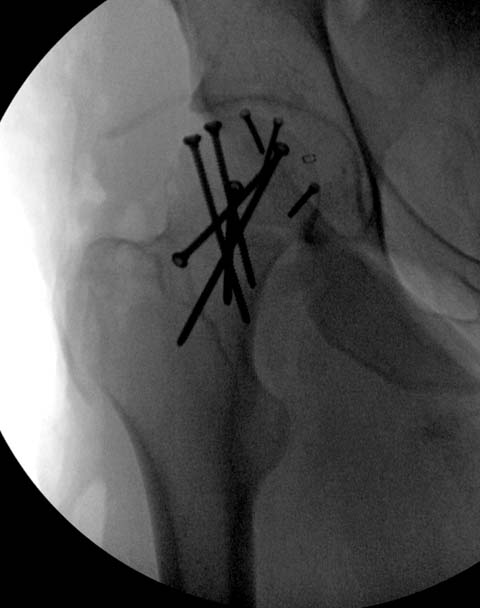

Далее перевод к нам в Травмоцентр и 03.03.2015. через 8 дней операция, выполнен остеосинтез головки 3-мя самокомпрессирующими винтами Autofix под разными углами с погружением в субхондральный слой. Доступ Kocher-Langenbeck с флип-остеотомией большого вертела и задним хирургическим вывихом головки бедра. В полости сустава два свободно-лежачих фрагмента хряща головки, которые были удалены. На снимках виден дефект хряща головки после репозиции. Небольшой фрагмент заднего края фиксирован двумя спонгиозными винтами. Далее шов раны с дренированием. На 2 сутки пациент поворачивался на здоровый бок с валиком между ног, на 4 сутки сидел в кровати и на 6 сутки ходил с помощью костылей.

Здесь выбрана правильная тактика и операция сделано на хорошо. Надеюсь, промах с фиксацией не создаст проблему. Можно было добавить в задную стенку spring plate и винты до медиального кортекса в фиксации вертела.

Здесь клинические примеры: Первый случай передний доступ, второй с ICP monitor Flipp Trochanteris

и с переломом заднего края.